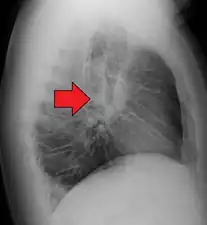

Hilar adenopathy especially on the person's left (AP CXR)

Hilar adenopathy especially on the person's left (lateral CXR)

Chest radiograph changes are divided into four stages:[104]

- bihilar lymphadenopathy

- bihilar lymphadenopathy and reticulonodular infiltrates

- bilateral pulmonary infiltrates

- fibrocystic sarcoidosis typically with upward hilar retraction, cystic and bullous changes

Although people with stage 1 radiographs tend to have the acute or subacute, reversible form of the disease, those with stages 2 and 3 often have the chronic, progressive disease; these patterns do not represent consecutive "stages" of sarcoidosis. Thus, except for epidemiologic purposes, this categorization is mostly of historic interest.[28]